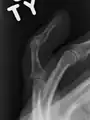

Mallet finger of the middle finger. The tip of the finger bends downwards while the other fingers stay straight.

A mallet finger usually results from overbending of the finger tip.[3] Typically this occurs when a ball hits an outstretched finger and jams it.[3] This results in either a tear of the tendon or the tendon pulling off a bit of bone.[3] The diagnosis is generally based on symptoms and supported by X-rays.[3]

The diagnosis is generally based on symptoms and supported by X-rays.[3] The injury can be accompanied by swelling and ecchymosis.[4]